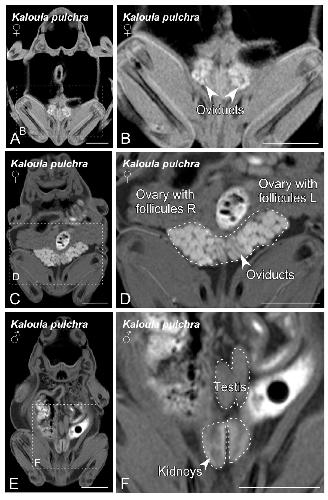

Sex Determination in Two Species of Anuran Amphibians by Magnetic Resonance Imaging and Ultrasound Techniques. , Ruiz-Fernández MJ, Jiménez S, Fernández-Valle E, García-Real MI, Castejón D, Moreno N , Ardiaca M, Montesinos A, Ariza S, González-Soriano J., Animals (Basel). November 18, 2020; 10 (11):